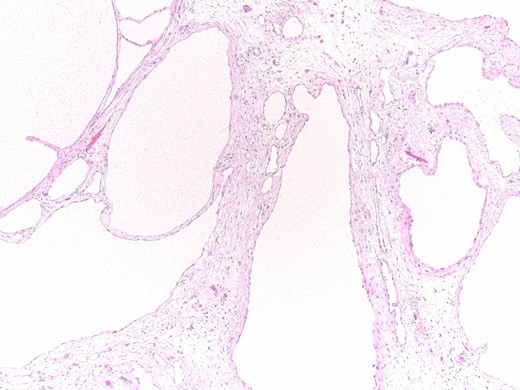

Histopathology results: cysts lined by flattened/cuboidal mesothelial cells.

Microscopically, the cysts of BMPM are lined by cuboidal or flattened mesothelial cells. In the latter case, BMPM could simulate the appearance of a cystic lymphangioma, but the former exhibits mesothelial markers, such as calretinin and WT1. Ross et al. [10] believe that BMPM is probably the result of a peritoneal reactive proliferation, forming multiple peritoneal inclusion cysts, and not a true neoplasm. The natural history of this disorder, with its great tendency to local recurrence and its tumor-like appearance, suggests its neoplastic pathogenesis, but both of the hypothesis can be argued.